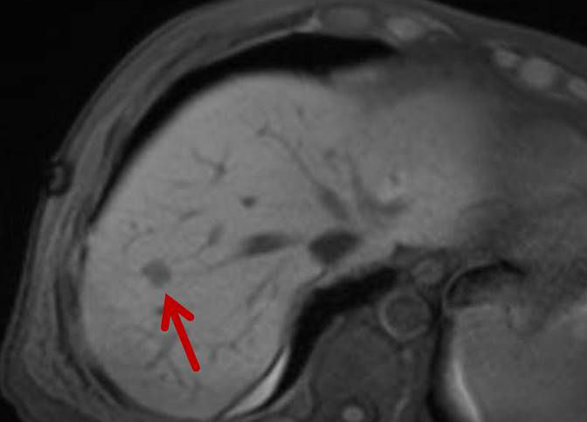

Eine Voraussetzung für die vollständige chirurgische Entfernung von Knochen- und Weichteiltumoren ist die präzise Erkennung der Tumorausdehnung und der Tumorgrenzen. Mit der Kernspintomographie (MRT) kann das Tumorgewebe exzellent von gesundem Gewebe abgegrenzt werden und somit die Ausdehnung vor der Operation bestimmt werden. Nach der kernspintomographischen Bestimmung der Tumorausdehnung werden unter kontinuierlicher MRT-Bildgebung die Grenzen des Tumors markiert. Die Marker werden mit einer Nadel ins angrenzende gesunde Gewebe eingebracht. Die Markierung kann am Tage vor der Operation durchgeführt werden. Alternativ ist die Tumormarkierung auch mit anderen bildgebenden Verfahren möglich, z.B. mit der Computertomographie oder dem Ultraschall.

Abbildung: Bei diesem Patienten wurde ein im Röntgen nur schlecht sichtbarer Knochentumor vor der Operation unter MRT-Kontrolle mit kleinen röntgendichten Spiralen („Coils“) markiert. Damit hat der Operateur eine optimale Darstellung des Tumorbereichs bzw. der Tumorgrenzen und kann gezielter, schonender und effektiver operieren.